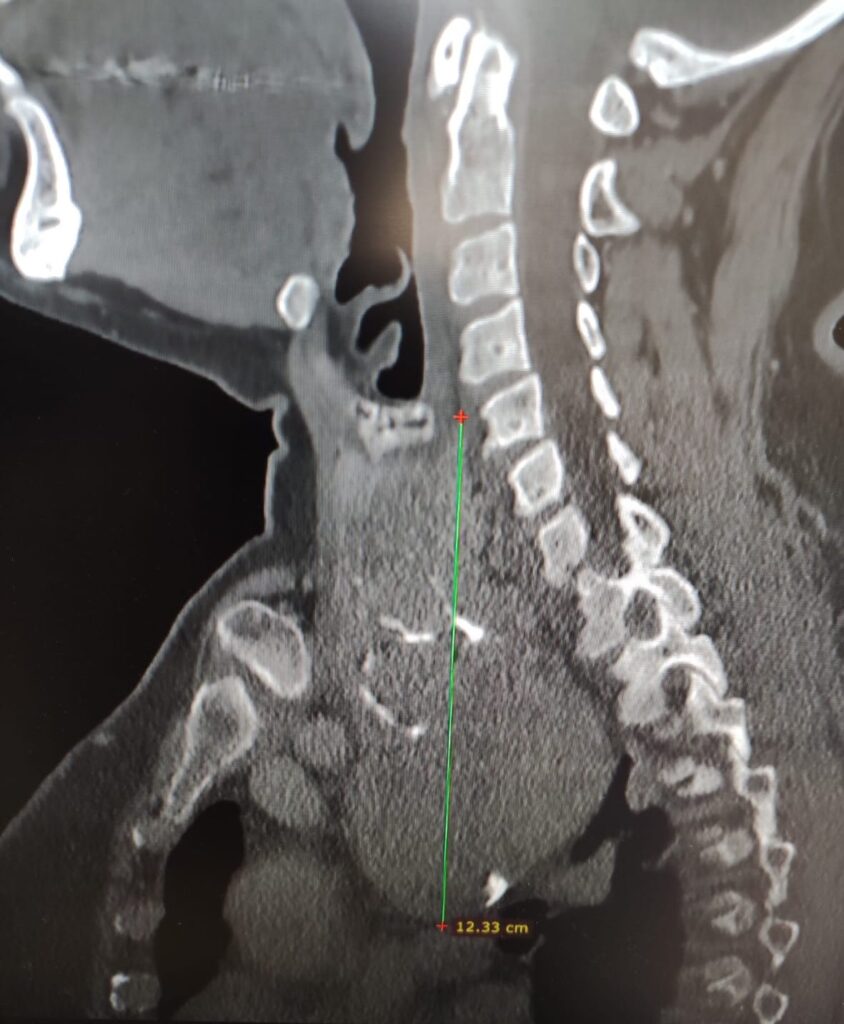

“Gli accertamenti radiologici – spiega il dottor Luigi Madami, otorinolaringoiatra che ha eseguito l’intervento nell’Unità operativa diretta dal prof. Nicola Quaranta – hanno mostrato che la tiroide era ingrandita, con un’estensione di circa sette centimetri, si estendeva nel mediastino (la parte alta del torace) e spingeva la trachea verso sinistra, pur lasciandola libera nel passaggio dell’aria. Erano presenti anche piccoli noduli e calcificazioni. L’intervento di rimozione della tiroide (tiroidectomia) è stato eseguito con un approccio sternotomico, cioè aprendo parzialmente lo sterno grazie alla collaborazione multidisciplinare con i cardiochirurghi”.

In foto: da destra la dottoressa Toraldo anestesista, il dott. Madami capo equipe, la dottoressa De Palo cardiochirurgo e il dottor Monda aiuto chirurgo e le immagini dell’estensione del gozzo endotoracico